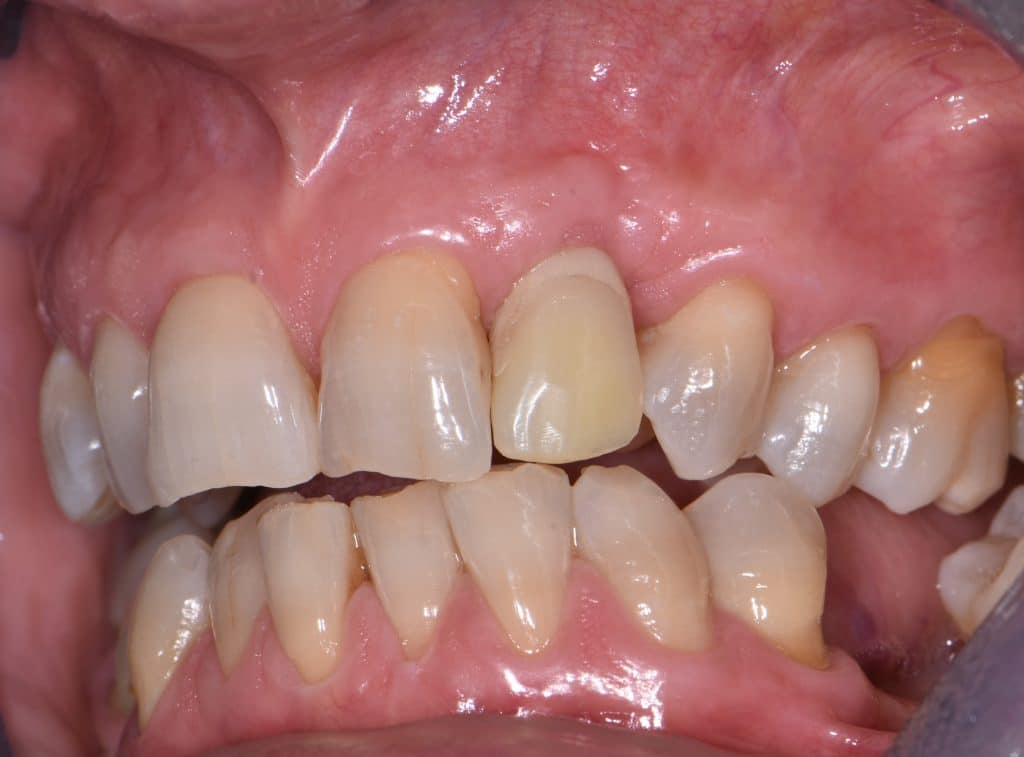

La pz N.G. di anni 52 (ASA 1) viene visitata nel mese di settembre 2017 per la mobilità ed inestetismo dell’elemento protesico 22, (foto iniziali sequenza 1) si evidenzia una frattura parziale della radice, si decide per l’estrazione ( foto sequenza 2) e sostituzione dell’elemento con un restauro implanto-protesico. Purtroppo la scarsa quota ossea apicale all’alveolo post-estrattivo (foto 2 rx) e l’alta valenza estetica dell’elemento ci rende cauti e si programma una socket preservation post estrattiva con l’ausilio delle membrane di prf (foto prf e socket sequenza 3 e 4). Durente i 5 mesi di guarigione la pz porta una protesi parziale mobile (foto 5,2) , a guarigione del sito post estrattivo si evidenzia una buona conservazione dei volumi osseo-gengivali,(foto guarigione sequenza 6) se pur presente una recessione distale all’elemnto 21.Nel mese di febbraio 2018 si procede all’inserimento di un impianto max-stability 3,75x12mm disegnando un lembo anticipato palatino per consentire un aumento dei tessuti vestibolari suturando con tecnica rool flap e trasformando l’elemento parziale mobile in una corona singola a carico immediato sul moncone temporameo applicando i concetti protesici bopt , (foto impianto moncone protesi provvisoria sequenza foto 7-8-9). Durante il periodo di maturazione dei tessuti molli vengono apportate opportune modifiche ai profili del provvisorio al fine di dare maggior spazio al tessuto gengivale, ( fotosequenza 10).Dopo circa 2 mesi dal protesizzazione provvisoria si è proceduto alla realizzazione del manufatto protesico con tecnica chair side sirona con l’ausilio del t-base (foto sequenza 11-12-13), realizzando in una sola seduta una corona in disilicato, ottenendo un risultato più che soddisfacente (Foto 14). Nel controllo a 3 mesi dal carico definitivo si apprezza la perfetta conservazione dei livelli ossei e gengivali. (foto sequenza 15).concludo con un follow up a 18 . Tengo a sottolineare che un caso come questo è stato conducibile con buoni risultati solo grazie alla piena fiducia della pz e alla sua massima motivazione e collaborazione. Ad oggi la pz sorride soddisfatta del risultato. E questo rappresenta la massima ricompensa di chi dedica tutto se stesso alla professione.